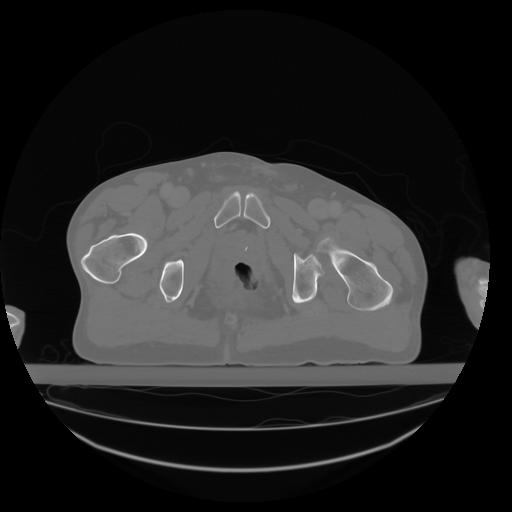

27 CUERPO,CE,Axial,3.0,CUERPO,,